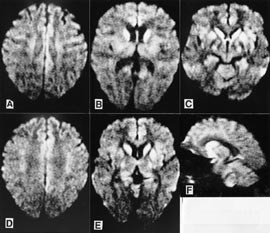

Pasienten. 54 år gammel kvinne. Hun hadde tidligere stort sett vært frisk, men gjennomgikk flere tannekstraksjoner og maksillærkirurgi det siste året før sykdomsdebut. De første symptomene var svimmelhet, asteni og vertigo, som tiltok gradvis. Åtte måneder senere utviklet hun ustø gange, eufori og raskt progredierende demens med desorientering, tap av korttidsminne og visuelle hallusinasjoner. Ved klinisk undersøkelse fant man nystagmus, ataksi, myoklonus, positiv mandibular og palmomental refleks og grav demens. Computertomografi (CT) av hjernen og blodprøver viste normale funn. EEG viste diffus dysrytmi med generalisert theta- og deltaaktivitet, men de typiske periodiske skarpe bølger som vanligvis sees ved Creutzfeldt-Jakobs sykdom, var ikke til stede. T2-vektet MR av hjernen viste ingen definitive avvik (fig 1). Diffusjonsvektet MR av hjernen viste markert økt signaldensitet, dvs. redusert diffusjon bilateralt i corpus striatum og gyrus cinguli (fig 2). Hun døde etter en måned i koma, 15 måneder etter debuten av de første symptomene. Diagnosen ble postmortalt bekreftet med utbredte, typisk spongiforme encefalopatifunn ved den histopatologiske undersøkelsen (fig 3). Prionproteingenanalyse viste ingen mutasjoner, men hun var homozygot for valin/valin i codon 129 (utført ved Creutzfeldt-Jakob Disease Surveillance Unit, Edinburgh, Skottland).

Dette tilfellet av Creutzfeldt-Jakobs sykdom er ett av få hittil rapporterte pasienter (8 – 12) som ble undersøkt med diffusjonsvektet MR. De patologiske forandringene man ser i diffusjonsvektet MR, er tydelige hyperintense signalavvik i basale ganglier og/eller cortex cerebri. Disse forandringene, som representerer redusert diffusjon grunnet funksjonsforstyrrelser i de aktuelle hjernedelene, ser ut til å være karakteristiske for Creutzfeldt-Jakobs sykdom. Det finnes ikke andre rapporterte tilstander med liknende diffusjonsforandringer. Diffusjonsvektet MR kan derfor være en undersøkelse som gir spesifikke funn for Creutzfeldt-Jakobs sykdom, og et nytt instrument i den premortale diagnostikken av denne sykdommen.